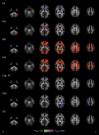

We identified a decrease of intracellular volume fraction (ICVF), decrease of isotropic volume fraction (ISO) and decrease of orientation dispersion index (ODI) in multiple inferior frontal regions of interest in COVID-19 patients; this longitudinal change was significantly different from the control group which demonstrated increases in equivalent measures. This pattern suggests injury with neuronal loss and/or inflammation as underlying mechanisms. Neurocognitive studies identified a pattern of cognitive decline (processing speed, executive function, verbal learning, working memory) in patients, that did not reach significance.